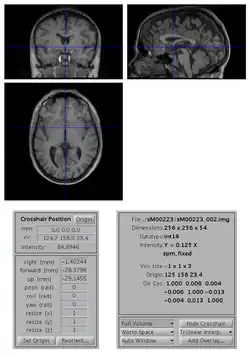

To change the origin of an image:

- open the image with SPM Display

- move the crosshair position so that it roughly points to the anterior commissure (AC).

- click on the Set Origin button

- click on the Reorient button and press done (your image is already selected). If you want to apply the same transformation to other images (e.g. if you have a series of functional images), select them all at this stage.

- say No to Do you want to save the reorientation matrix?

This will set the origin of the image (0 0 0 mm coordinates) to AC. You might also want to rotate the image such that it is better aligned with MNI space: to do so, you also need to edit the entries for the rotations (in radian) along the pitch, roll and yaw axes.